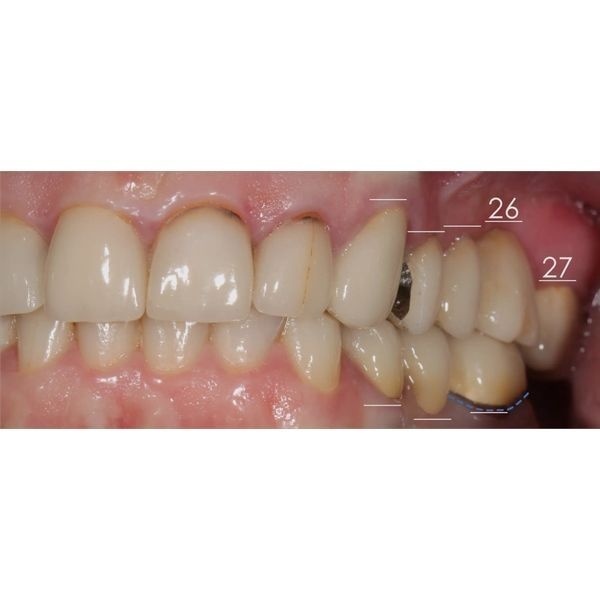

Пациентка хотела заменить старые ортопедические конструкции на центральных резцах (зубы 1.1, 1.2, 2.1 и 2.2), которым было уже более 7 лет, а также поменять сломанный мостовидный протез на верхней челюсти слева (зубы 2.3–2.7).

При моделировании будущих зубов использовались данные аксиографии: угол суставного пути (наклон ската суставной ямки), переднюю направляющую (угол наклона центральных зубов), угол окклюзионной плоскости по сфере Монсона (высота боковых зубов). После провели примерку будущих конструкций в полости рта. Когда всё согласовали (женщина скорректировала эстетические параметры — размер и форму), конструкции зафиксировали на пару месяцев и сделали контрольное МРТ. Она показала расширение суставной щели и более корректное положение суставной головки слева.

- установили 5 имплантов;